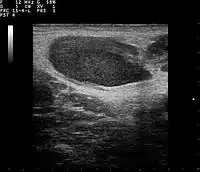

.jpg.webp)